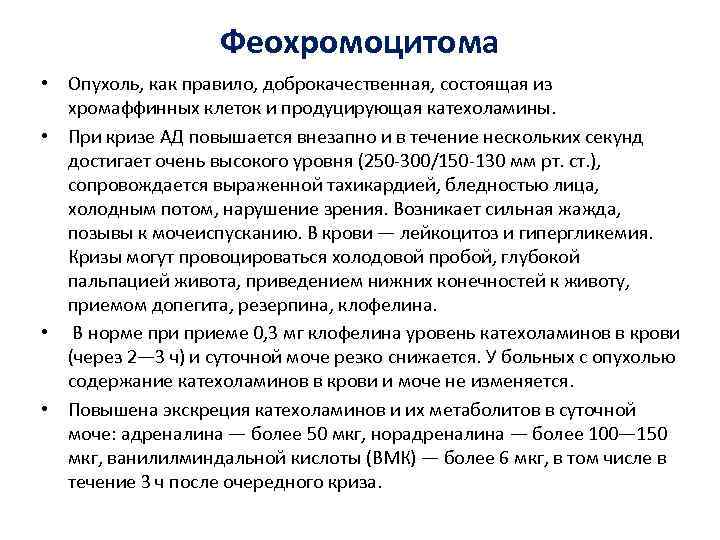

Феохромоцитома • Опухоль, как правило, доброкачественная, состоящая из хромаффинных клеток и продуцирующая катехоламины. • При кризе АД повышается внезапно и в течение нескольких секунд достигает очень высокого уровня (250 -300/150 -130 мм рт. ст. ), сопровождается выраженной тахикардией, бледностью лица, холодным потом, нарушение зрения. Возникает сильная жажда, позывы к мочеиспусканию. В крови — лейкоцитоз и гипергликемия. Кризы могут провоцироваться холодовой пробой, глубокой пальпацией живота, приведением нижних конечностей к животу, приемом допегита, резерпина, клофелина. • В норме приеме 0, 3 мг клофелина уровень катехоламинов в крови (через 2— 3 ч) и суточной моче резко снижается. У больных с опухолью содержание катехоламинов в крови и моче не изменяется. • Повышена экскреция катехоламинов и их метаболитов в суточной моче: адреналина — более 50 мкг, норадреналина — более 100— 150 мкг, ванилилминдальной кислоты (ВМК) — более 6 мкг, в том числе в течение 3 ч после очередного криза.

Феохромоцитома • Опухоль, как правило, доброкачественная, состоящая из хромаффинных клеток и продуцирующая катехоламины. • При кризе АД повышается внезапно и в течение нескольких секунд достигает очень высокого уровня (250 -300/150 -130 мм рт. ст. ), сопровождается выраженной тахикардией, бледностью лица, холодным потом, нарушение зрения. Возникает сильная жажда, позывы к мочеиспусканию. В крови — лейкоцитоз и гипергликемия. Кризы могут провоцироваться холодовой пробой, глубокой пальпацией живота, приведением нижних конечностей к животу, приемом допегита, резерпина, клофелина. • В норме приеме 0, 3 мг клофелина уровень катехоламинов в крови (через 2— 3 ч) и суточной моче резко снижается. У больных с опухолью содержание катехоламинов в крови и моче не изменяется. • Повышена экскреция катехоламинов и их метаболитов в суточной моче: адреналина — более 50 мкг, норадреналина — более 100— 150 мкг, ванилилминдальной кислоты (ВМК) — более 6 мкг, в том числе в течение 3 ч после очередного криза.